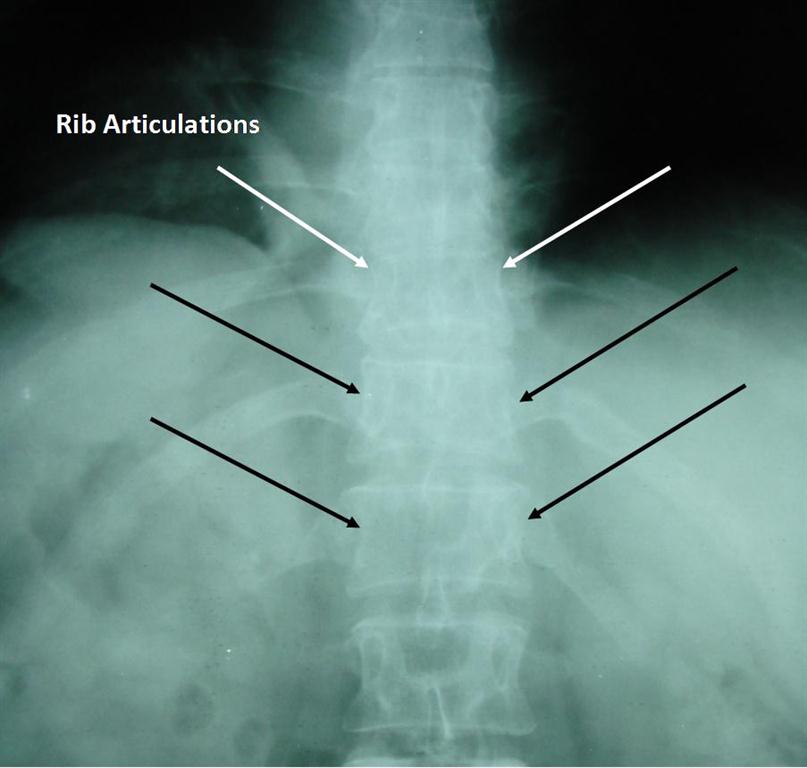

Thoracic spine pain originates in the mid-back between the cervical (neck) and lumbar (low back) spinal areas. The normal thoracic spine has a convex curve. Its 12 vertebrae attach to the ribs via articulations that assist in breathing and motion.

Ribs that surround and protect the chest organs connect to the sternum (chest bone) with cartilage. The ribs articulate or move with the thoracic vertebrae at the spine. The articulation of the rib to the thoracic vertebrae can be a source sharp, stabbing, or burning back pain.